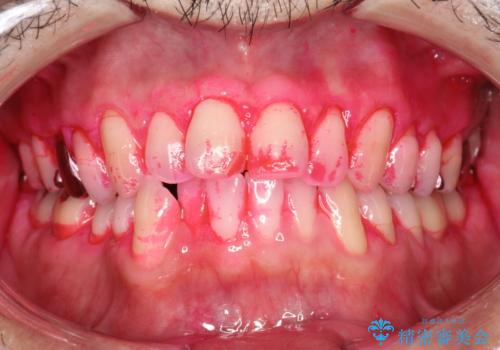

- 歯科でのクリーニングがかなり久しぶりで口臭も気になるとのことで来院されました。PMTCの60分コースで、染め出し・ブラッシング指導・クリーニングを行いました。

口臭は、様々なことからの原因がありますが、お口の中の細菌が繁殖することにより発生するともいわれています。多くの場合は正しい歯磨きを習慣づけることで、減少されます。毎日のご自身でのケアと、定期的に歯科医院にてPMTCを受けることにより、息をさわやかにすることができます。

適切な歯磨き方法を習得するには、染め出しを行い、磨き残しを把握していくことがポイントです。

磨けているよう、磨いているつもりでも、汚れが残ってしまうと、毎日の歯磨き時間が無駄になってしまうこともあります。効率的に歯磨きを行い、磨き残しを減らせるように、歯科衛生士による専門的な指導を行います。